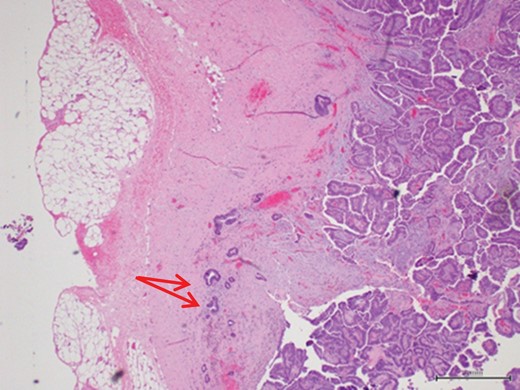

Ultrasound studies showed a well-defined solid-cystic nodule measuring approximately 2.1 cm × 2.1 cm × 1.4 cm with internal septation. There was a large, peripherally located solid component with internal vascularity seen (Fig. 2). The lesion was deemed indeterminate and an excision biopsy was performed. The histology report revealed a Grade 1 IPC with no lymphovascular invasion (Figs 3 and 4).

Scattered tubules (arrow) within the stroma with no extension beyond the fibrous wall. These scattered tubules measure 3 mm (magnification x4).